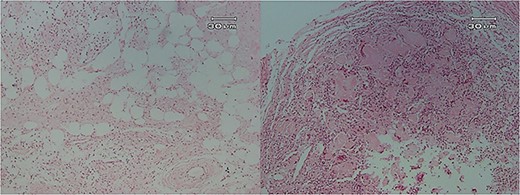

Microscopic examination showed (Figs 4–7) inflamed connective tissue composed of prominent plasma cells mixed with numerous osteoclastic multinucleated giant cells of various sizes with intracytoplasmic asteroid bodies and round Schaumann bodies, which surrounding round to amorphous eosinophilic areas composed of the spindle to stellate cells in fibromyxoid background is also evident.

Histopathologic views of the lesion (H&E staining, ×100 magnification). (A) Inflamed fibromyxoid connective tissue. (B) Area of one granulomatous pattern inflammation with multiple giant cells. (C) Numerous foreign body giant cells admixed with severe chronic.

Histopathologic views of the lesion (H&E staining×100 magnification) showing chronic inflammatory cells admixed with multinucleated giant cells of varying sizes.